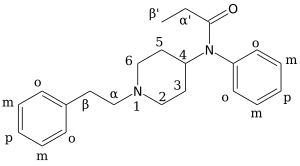

Chemical structures of various fentanyl analogues

Organic chemistry

Because there are so many analogues of fentanyl, the naming for them tends to follow classical or IUPAC nomenclature conventions. This section is written to help illustrate the basic ring structure of fentanyl and what popular analogues reference on the carbon skeleton, helping a chemist working with fentanyl analogues quickly and consistently navigate the nomenclature system.

- Part I

The synthesis of fentanyl and its analogues are illustrated in these skeletal diagrams. The synthesis of fentalogs is done by reacting the ring structure as a base, 4-ANPP also called 4-anilino-N-phenethylpiperidine and despropionylfentanyl. 4-ANPP acts as a base because of its two amine nitrogens, the secondary amine acts as a base to react with an organic acid which condenses into an amide. Depending on the organic acid used in the amide condensation, different analogues of fentanyl will be produced. To help align this phenomenon in the eyes of chemists, we have numerated the precursor 4-ANPP with a [0.], and then the reactions synthesizing fentanyl, acetylfentanyl, butyrylfentanyl, and benzoylfentanyl with a [1.], [2.], [3.], and [4.] respectively. To further aid in the chemical pedagogy we have aligned each number with a reaction number -> precursor -> product system that follows the following scheme: EXAMPLE: reaction number -> precursor -> product [compound name] 1 -> α -> a [fentanyl] 2 -> β -> b [acetylfentanyl] 3 -> γ -> c [butyrylfentanyl] 4 -> δ -> d [benzoylfentanyl]

Using the above scheme, a chemist can quickly extrapolate the reactions necessary for other fentanyl analogues with more complex organic acids, such as cyclopropryl fentanyl or cyclopentyl fentanyl, or any other fentanyl analogue derived from a reaction of 4-ANPP with a novel organic acid.